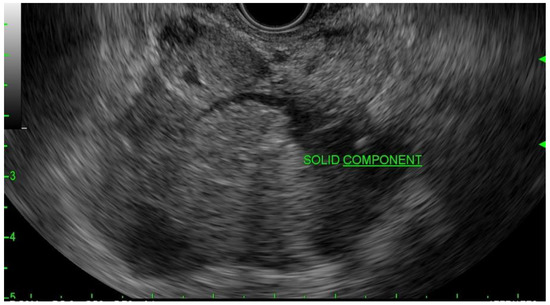

IPMNs can be divided into main duct intraductal papillary mucinous neoplasm and branch duct intraductal papillary mucinous neoplasms, with dilation of the main pancreatic duct helping to distinguish between the two. They usually present in the fifth to seventh decade of life and have an equal distribution between males and females [15]. Intraductal neoplasms are typically associated with a dilated main pancreatic duct (Figure 2a,b), whereas the branch duct IPMNs are associated with a dilated pancreatic duct branch or branches (Figure 3). A mixed IPMN is defined as a cystic lesion with ductal communication and main pancreatic duct dilation greater than or equal to 5 mm (Figure 4). Diabetes mellitus (DM) and a family history of pancreatic adenocarcinoma are known risk factors for IPMN, with odds ratios of 1.79 (CI 95%: 1.08–2.98) and 2.94 (CI 95%: 1.17–7.39), respectively [16]. Cytology can show columnar cells with variable atypia and can stain positive for mucin. CEA is usually greater than 200 ng/mL in approximately 75% of lesions, similar to mucinous neoplasms. Main duct IPMNs have a 36–100% risk of malignant potential, compared to a lower risk of 11–30% malignant potential of side branch IPMNs [17].

Figure 2.

(a) EUS image of main duct IPMN; (b) MRI image of main duct IPMN.